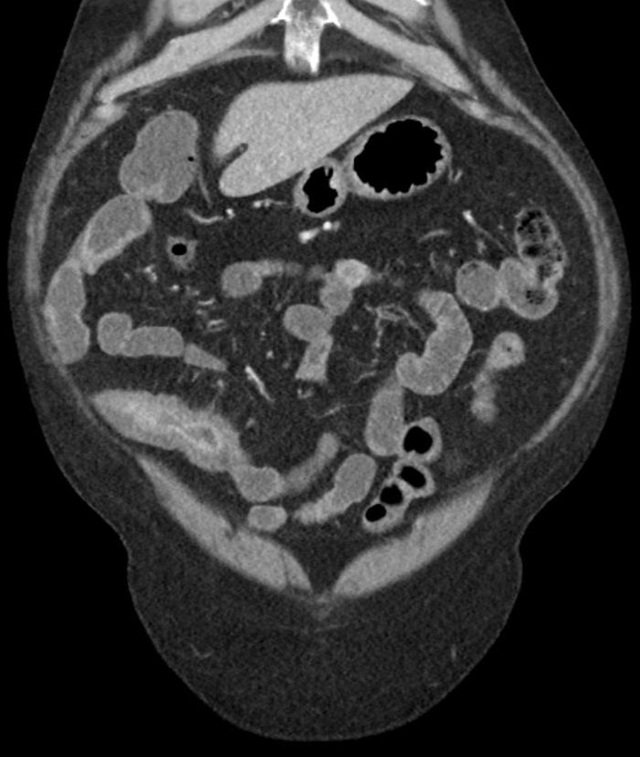

想象一下,你正享受着美食,突然间肚子开始剧痛,那种痛,就像是被无数小刀在肚子里乱砍。你以为只是简单的消化不良,但其实是克罗恩病在作祟。这种病,让人无法预测,无法控制,它可以在任何时候,任何地点,给你致命一击。

但你知道吗?克罗恩病并不是绝症,虽然它无法根治,但通过合理的治疗和管理,很多患者依然可以拥有相对。